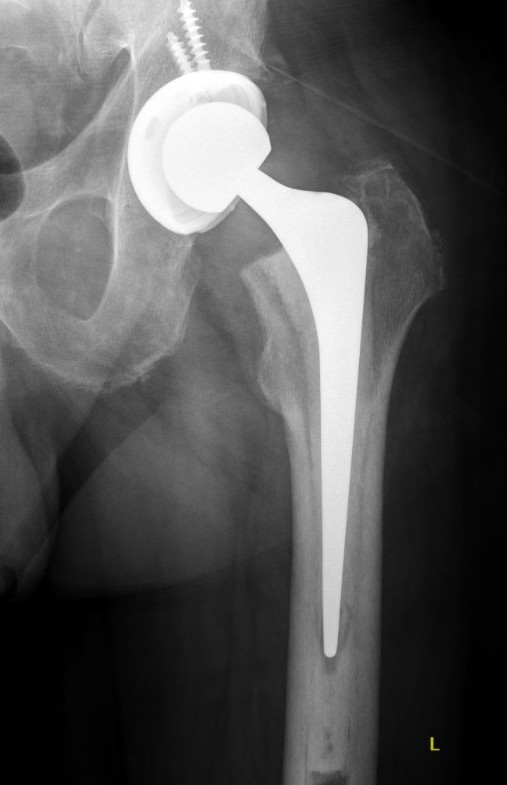

Fracture with stem subsidence around a polished tapered femoral stem treated with ORIF